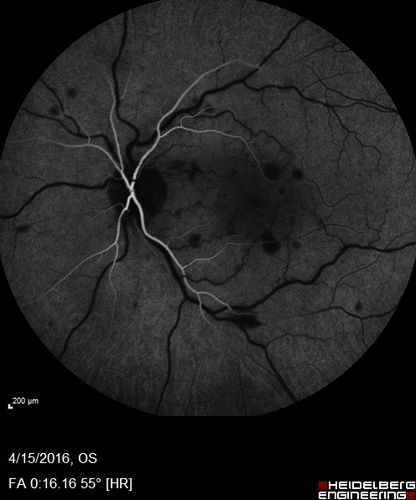

Central retinal artery and vein occlusion - Protein C Deficiency 33 year old male

33 year old male with vision loss for 3 hours.  VA 20/12 right eye, 5/200 left eye.  He has a protein C deficiency.  The left eye recovered vision in about 1 month to 20/16.  FA shows very slow recirculation time.